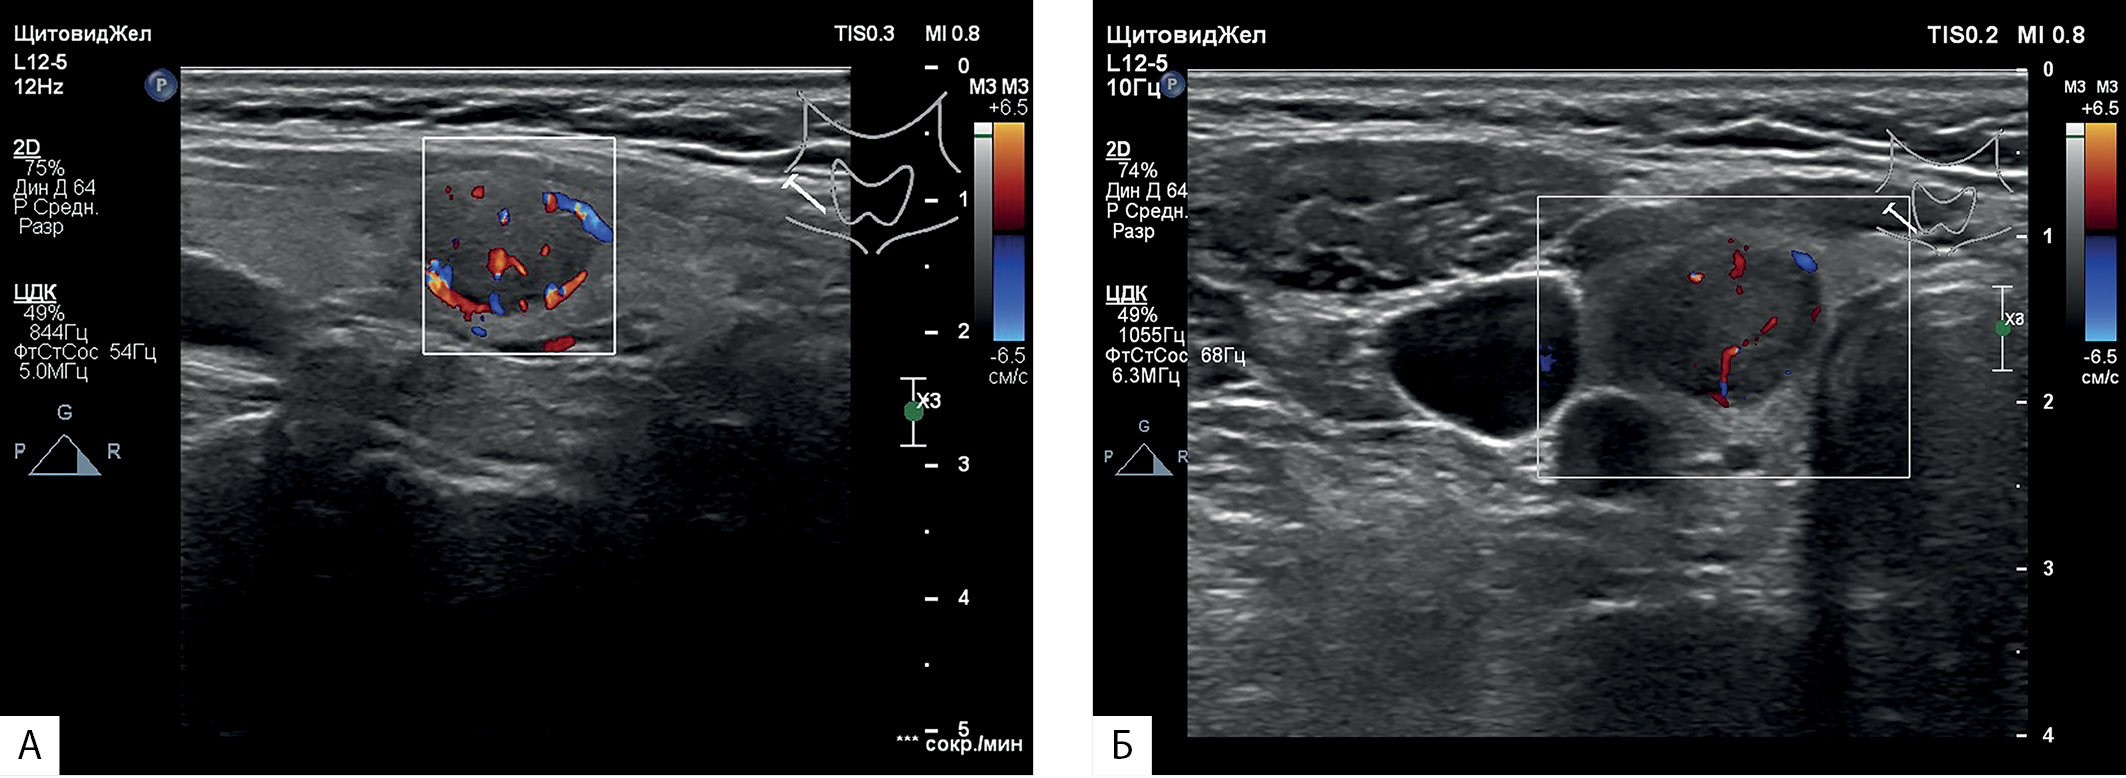

1. Рисунок 1. Ультразвуковое изображение правой доли щитовидной железы в В-режиме с использованием цветного допплеровского картирования: А — продольное сканирование; Б — поперечное сканирование. | |